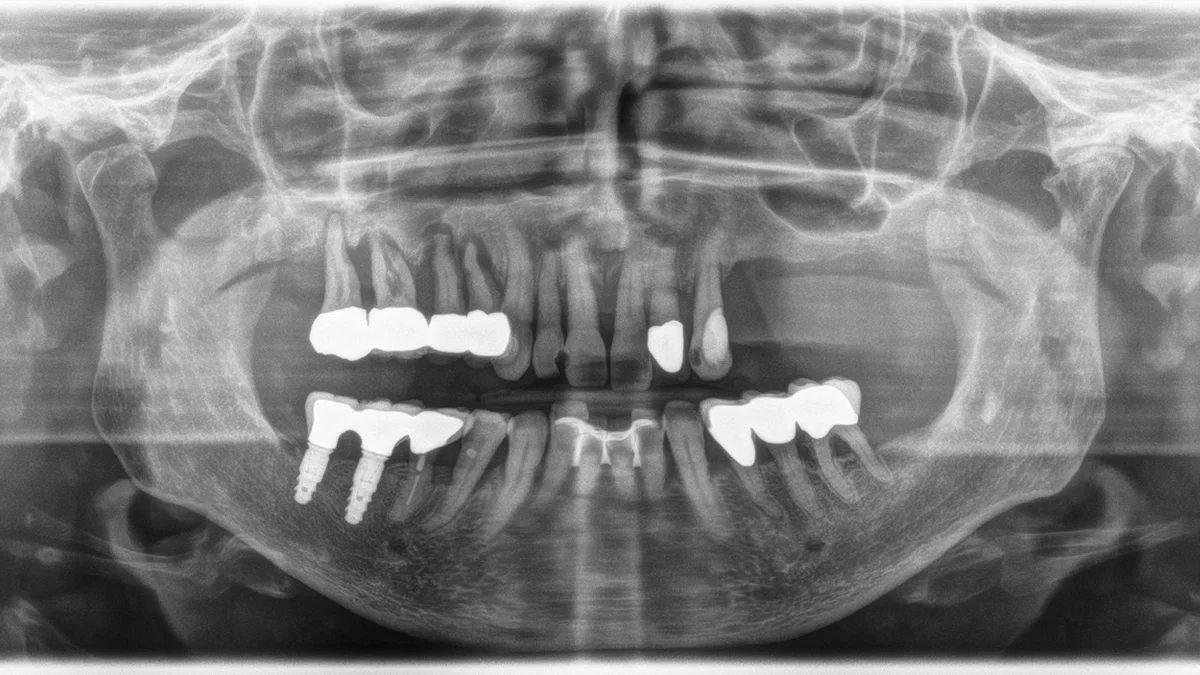

Full mouth implants are planned digitally, placed precisely, and restored with teeth designed to look and feel natural.

Digital 3D scan & planning

We assess bone, bite and smile design before surgery so the implant position supports the final teeth.

Implants placed

Implants are positioned carefully to support a secure full arch restoration.